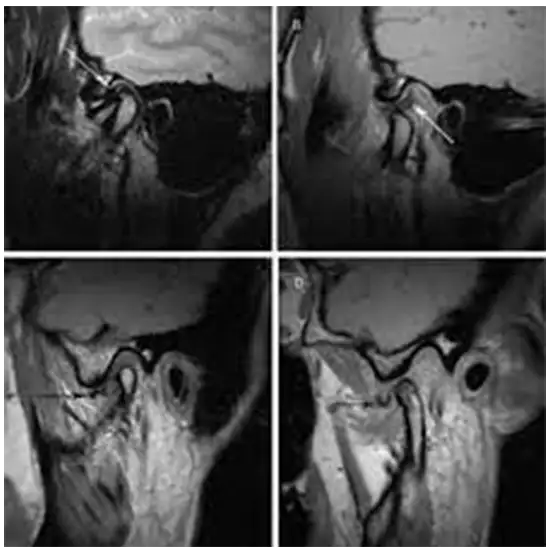

An MRI of the TMJ (temporomandibular) joint shows the area where your lower jaw meets your skull and the soft tissues around it.

MRI (Magnetic Resonance Imaging) screening of the TM Joint is a non-invasive radiology test used to evaluate the condition of the TM Joint and surrounding tissue. MRI TM Joint is done to look for its condition and surrounding area.